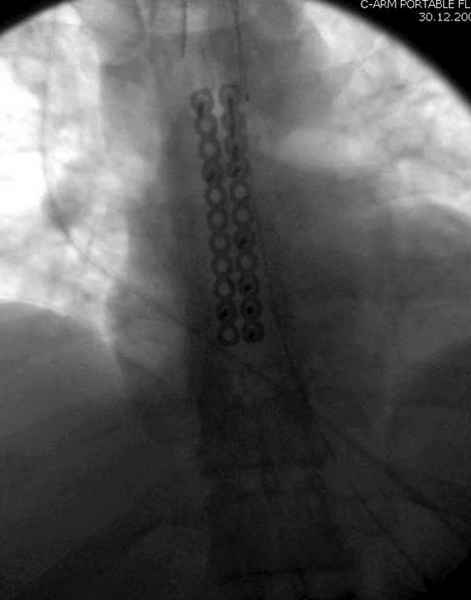

"классический" остеосинтез проволокой, иногда подкладываю шайбы, чтобы не прорезалась

А простые посттравматические ложные суставы грудины приходилось оперировать с ограничителем сверла и с фиксацией 2.4 мм пластинами с угловой стабильностью.